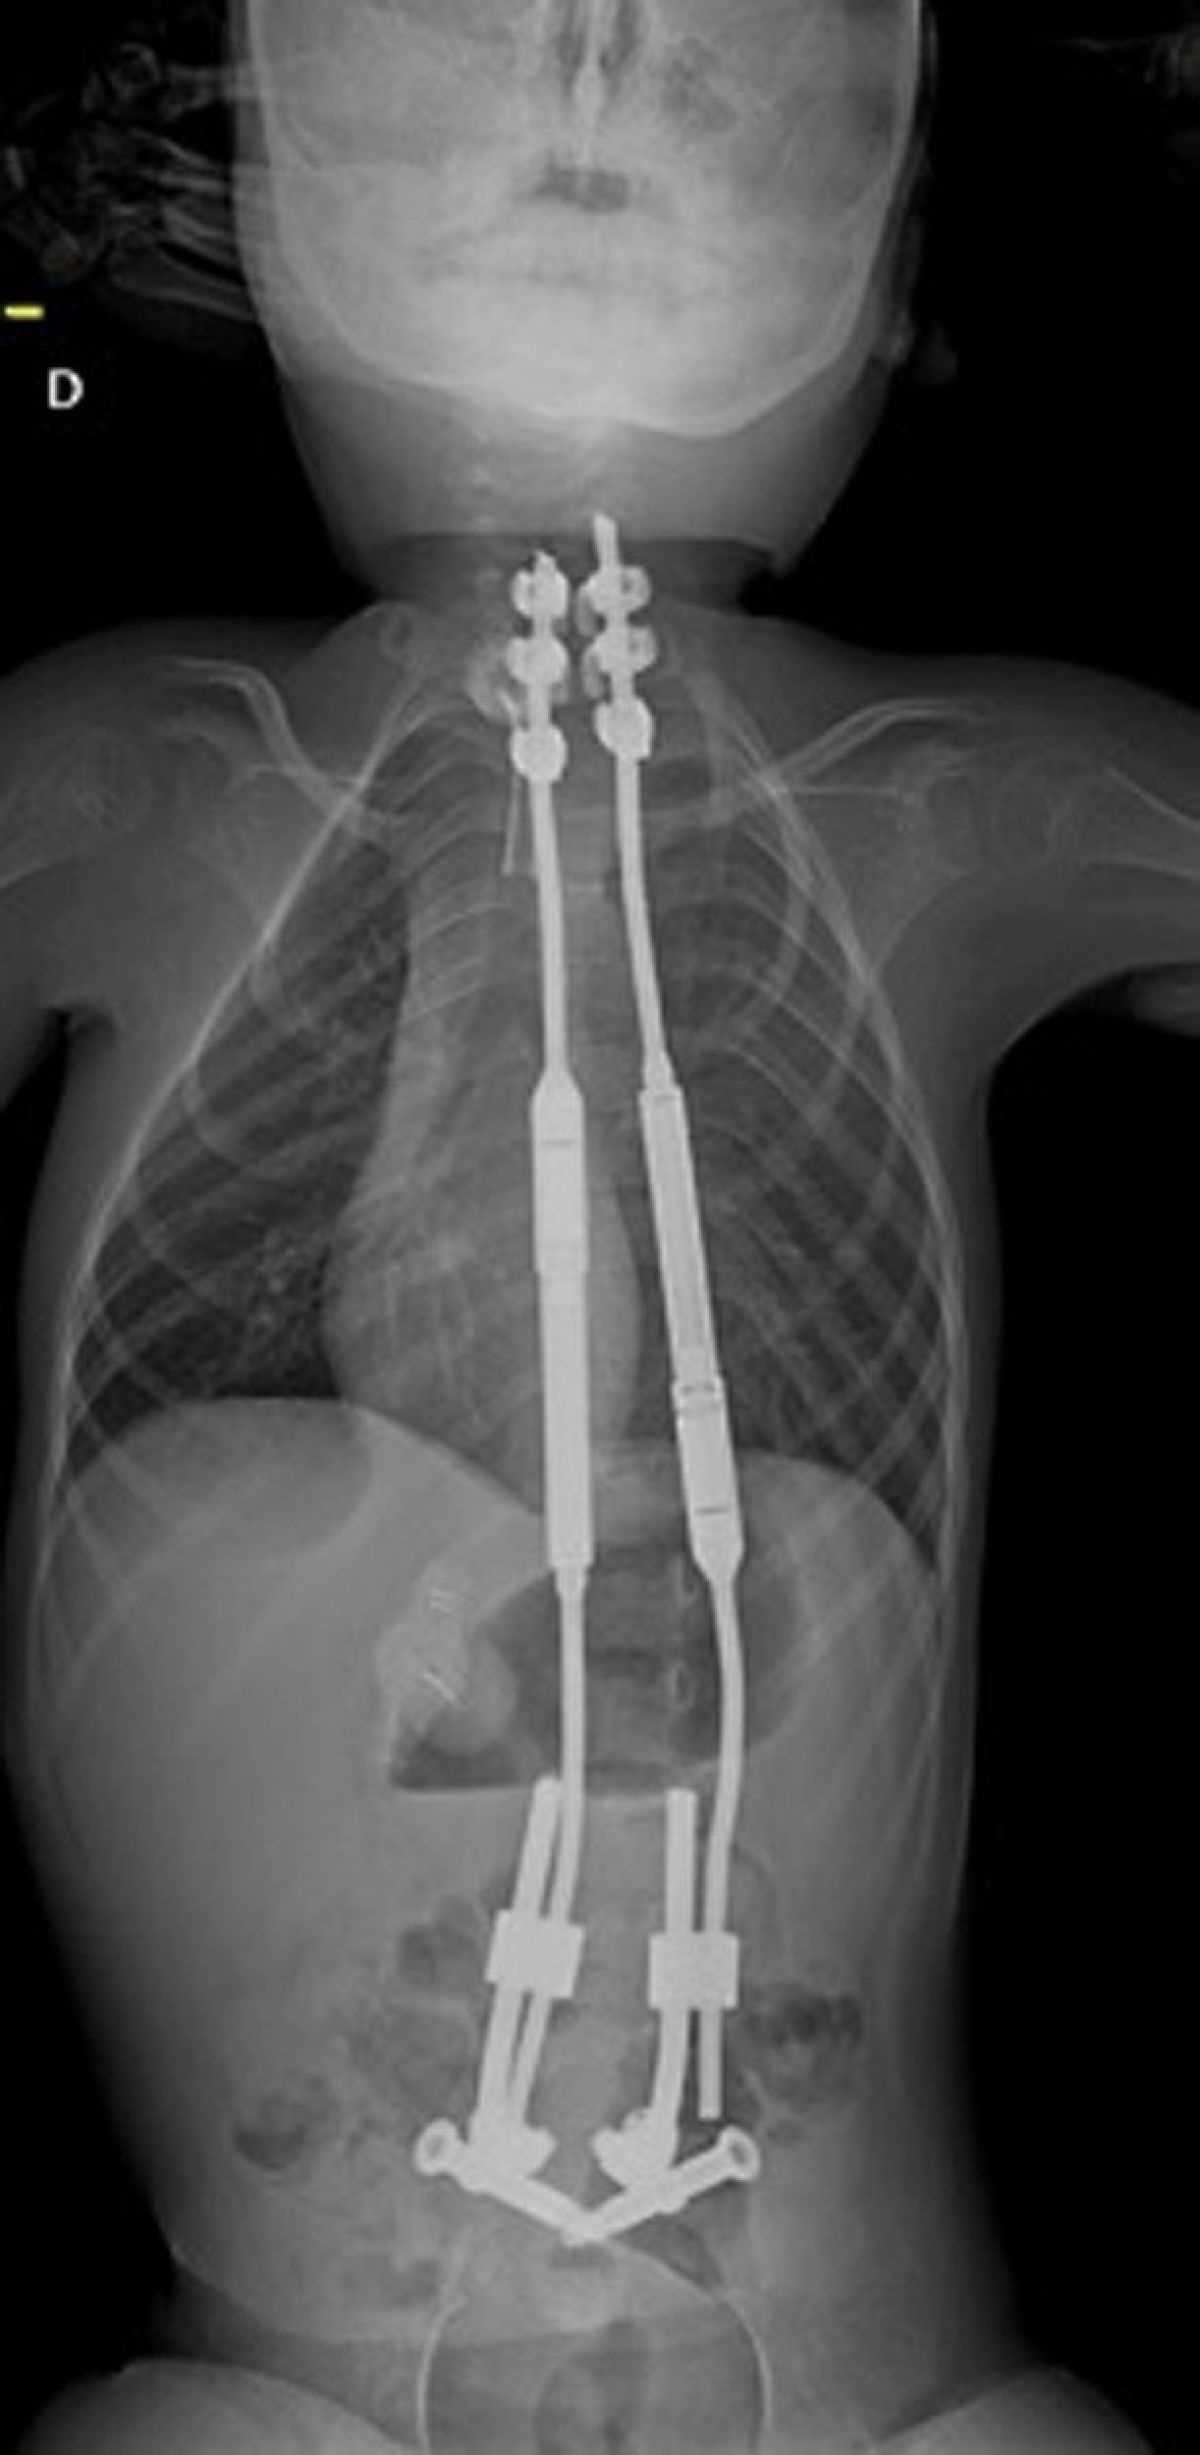

Deček trpi za hudo obliko skolioze (po operaciji).

Deček je trpel za hitro napredujočo skoliozo in spinalno mišično atrofijo. Skolioza oziroma ukrivljenost hrbtenice je napredovala že do te mere, da deček ni mogel več niti sedeti.

Kirurgi so zapleteno operacijo, ki so jo nato izvedli 28. septembra, načrtovali leto dni. Najprej so s pomočjo 3D tiskalnika izdelali natančno repliko dečkove hrbtenice, ki so jo nato vstavili v lutko ustrezne velikosti. To je kirurgom omogočilo, da so podrobno proučili potek operacije in jo celo simulirali. Na podlagi tega so lahko izbrali vsadke pravilne velikosti in testirali kirurškega robota.

Preberite še

Med zahtevnim posegom, ki je trajal tri ure, so s pomočjo majhnih vrezov v dečkovo hrbtenico vstavili vsadke. Ker je bila potrebna izjemna natančnost, so si pomagali z robotom, s katerim so v hrbtenico na točno določena mesta, ki so jih izbrali kirurgi, zavrtali in tja namestili vijake. »Vstavljanje vijakov v bližino korenin živcev je še vedno zelo zapleteno in redko; vijaki so v primerjavi z majhnostjo otroških kosti zelo veliki. S pomočjo robota Rosa smo lahko prvič poenostavili operacijo in skrajšali čas njenega trajanja,« so pojasnili.

Deček po operaciji dobro okreva in domnevno lahko že normalno sedi. Revolucionarno operacijo naj bi sicer izvajali zgolj v skrajnih primerih, nanjo pa trenutno čakajo štirje otroci.